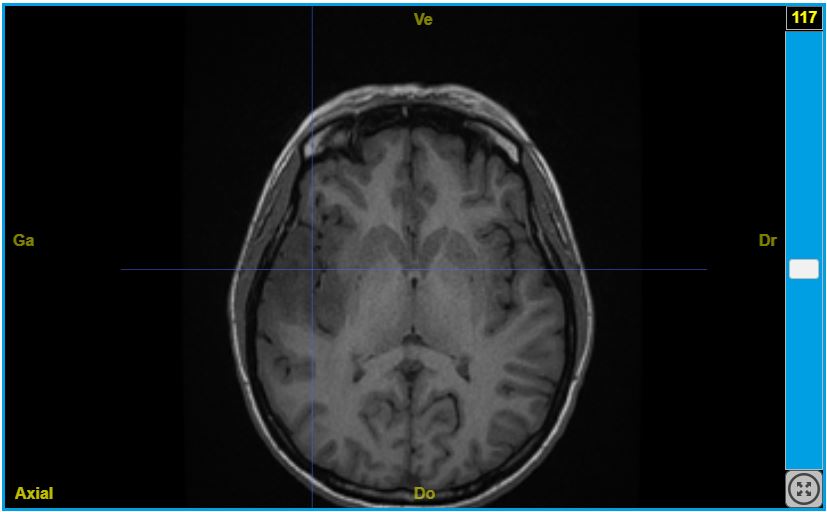

IRM en pondération T1 montrant l’emplacement de la tumeur dans l’hémisphère gauche. Une IRM en pondération T2 (contraste inversé attention) est également disponible.